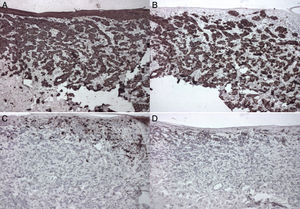

El estudio histológico de la lesión mostró la presencia de una infiltración dérmica difusa por células tumorales epiteliales con un moderado pleomorfismo celular y nuclear. Por sectores conforman estructuras ductales, y en otras las células tumorales se disponen en fila india. La infiltración tumoral comprometía la epidermis, con un marcado epidermotropismo. Se observaba la presencia de pigmento en las células tumorales superficiales y la dermis superficial (fig. 2).

La inmunohistoquímica fue positiva para citoqueratina (CK): CK7 y negativa para S100, HMB45, Melan-A y CK20 (fig. 3). Presentaba una positividad focal para los receptores de estrógenos y de progesterona, y negativo para Hercep test®.

En la histopatología de las metástasis de cáncer de mama se evidencia un compromiso de la dermis por las células tumorales, que pueden disponerse en forma individual, en fila india entre los haces de colágeno, conformando cordones, nidos, estructuras glandulares o agregados sólidos. A mayor aumento estas células muestran unos núcleos poligonales, hipercromáticos y pleomórficos. Las metástasis pigmentadas de cáncer de mama presentan conexión con la epidermis y ascenso pagetoide, tanto de células individuales como de nidos irregulares. Las células tumorales intraepidérmicas y dérmicas contienen melanina en su citoplasma, y también se evidencian numerosos melanófagos dérmicos4,9.

Los carcinomas de mama generalmente presentan un patrón CK7 positivo y CK20 negativo. La tinción para proteínas S100, HMB45 y Melan-A en la mayoría de los casos son negativas, esto lo diferencia del melanoma ya que este último suele expresar estas proteínas. También se pueden utilizar receptores hormonales para estrógeno y progesterona.